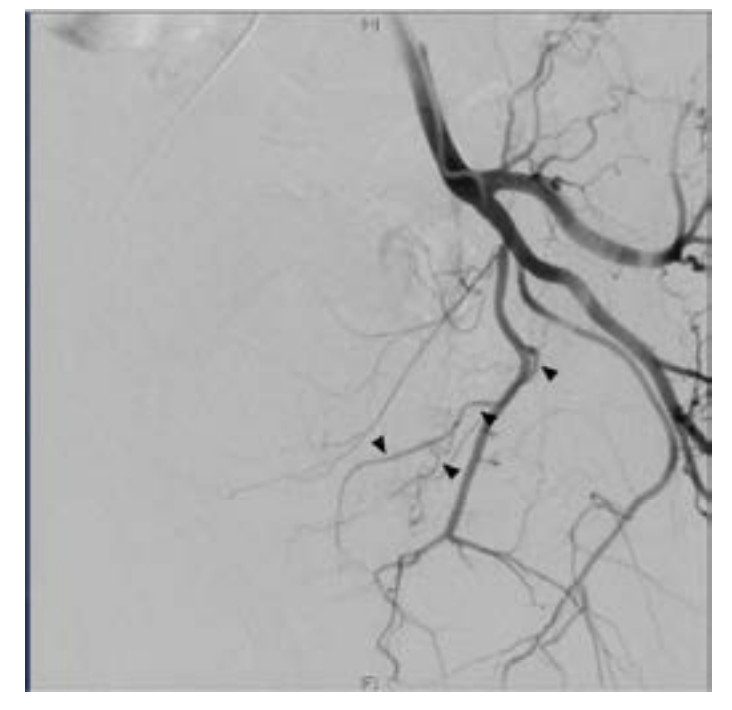

A 74-year-old male with past medical history of hypertension, coronary artery disease, and BPH with LUTS refractory to medical management presented for evaluation. The patient underwent an MRI of the prostate demonstrating a 182 cc gland with an enlarged transitional zone measuring 144 cc (Figure 1). The patient’s baseline IPSS and QoL were 18 and 5, respectively. Given the patient’s prostate gland size, and medical comorbidities, he elected to undergo PAE for management of his LUTS. On the day of his PAE, right common femoral arterial access was obtained and a pigtail DSA was obtained delineating pelvic arterial anatomy. On the right, the prostatic artery arose from a vesiculoprostatic trunk, with a shared origin with the superior vesicular artery (Figure 2). This was selectively catheterized with a progreat alpha microcatheter (Terumo, Tokyo, Japan), and 016” fathom microwire (Boston Scientific, Marlborough, MA). Angiography demonstrated perfusion of the entire right portion of the gland, without evidence of extra-prostatic supply (Figure 3). Embolization was performed with 300-500 micron Embospheres (Merit Medical, South Jordan, UT) to stasis. On the left, the prostatic artery arose from the left obturator artery (Figure 4). This was subsequently catheterized with the same catheter/wire combination, with angiography demonstrating left glandular perfusion without extra-prostatic supply (Figure 5). Embolization was again performed to stasis with 300-500 micron Embospheres. The patient did well post-procedurally with self-limited urinary frequency and dysuria for 3 days. By 3 months post PAE, the patient reported a significant improvement in his LUTS, with an IPSS/QoL of 3 and 0, respectively.